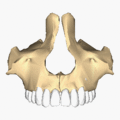

Front view. Maxilla visible at center, in yellow.